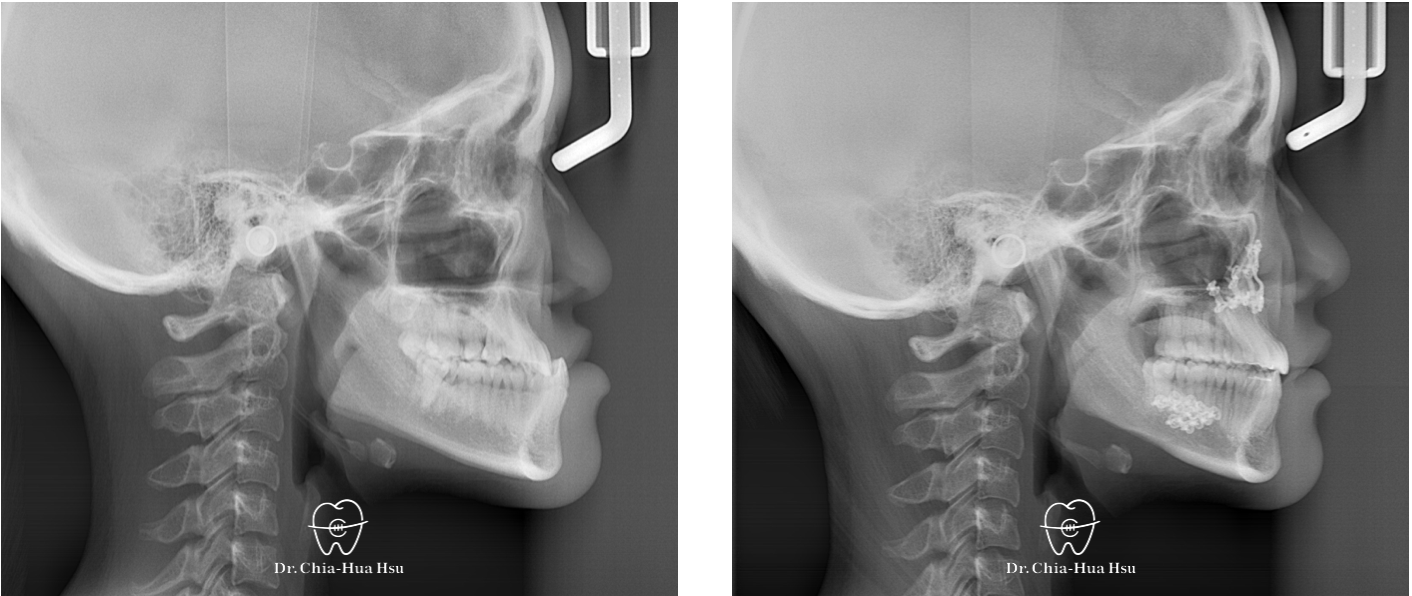

• 20多歲的日籍大學生小時候有做過矯正治療,不過下顎骨隨著年紀持續生長,變成戽斗且開咬的樣子。於是,患者接受了矯正合併正顎手術,不但改善外觀,也改善了咬合功能與牙齒排列(患者很開心可以咬斷麵條)。

• 病患主訴:戽斗、前牙開咬。

• 問題分析:患者是標準的骨骼三類咬合(Skeletal Class III),下巴明顯較長,還有上顎牙弓過窄、開咬以及齒列不正。

• 治療方式:使用傳統金屬矯正器,合併正顎手術(雙顎),上顎拔除兩顆小臼齒以利手術方式進行上顎牙弓擴寬。

• 治療時間:1 年 7 個月。

• 治療結果:齒列排齊,咬合功能恢復,外觀更和諧。